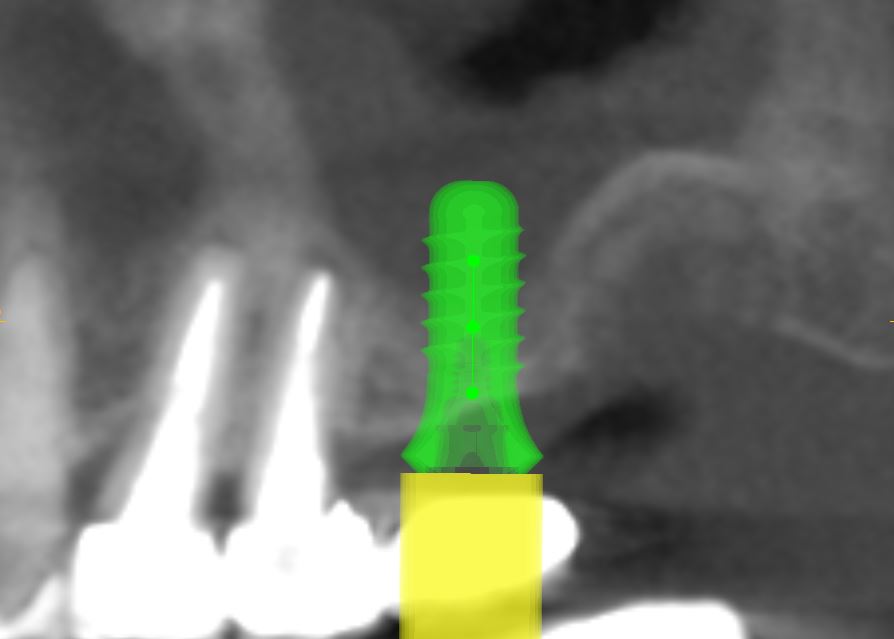

Le sinus lift (accès par voie latérale) : lorsqu’il manque de l’os en arrière du maxillaire supérieur, on accède au sinus par une paroi latérale et on le comble avec nos matériaux. Cela augmente la hauteur osseuse disponible.

Le push-back (apport par voie crestale) : cette méthode permet d’apporter de l’os par le trou de forage lors de la pose de l’implant.